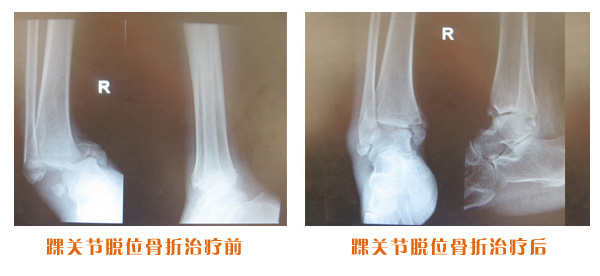

肥城市安駕莊梁氏骨科醫院是一所以梁氏手法正骨配合膏藥為特色的現代化??漆t院。

梁氏骨科術始創于清雍正年間,歷經八代,至今已有三百年歷史。據1929年泰安縣志載“梁瑞圖先生,字增生,號蓮峰,安駕莊人,精岐黃并發(fā)明接骨,凡跌打車凡跌打車軋皮不破而碎骨者......【詳細】 |